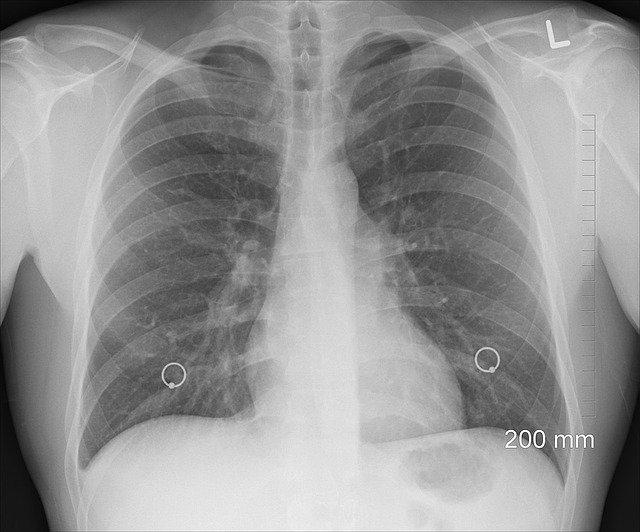

2. Pľúca

Kapacita pľúc žien je približne o 30 percent nižšia ako u mužov